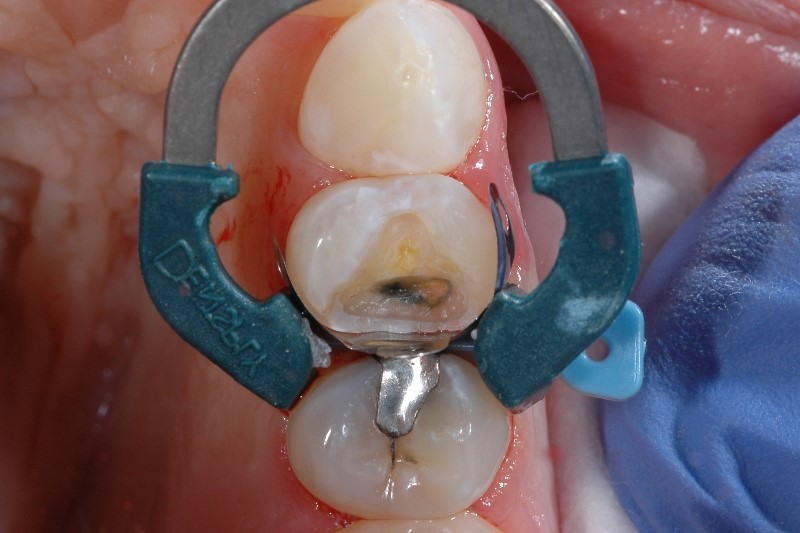

Sensibilità causata da un isolamento dentale inadeguato

Il corretto isolamento dei denti è fondamentale in qualsiasi fase del restauro di Classe II, in quanto impedisce alla saliva e al sangue di contaminare il campo operatorio. Se il campo operatorio è contaminato, le proprietà fisiche e il successo finale del restauro possono essere compromessi, causando sensibilità post-operatoria e disagio nel paziente.

Come evitare la sensibilità causata da isolamento inadeguato del dente

I problemi di isolamento sono molto comuni: il 97% dei medici afferma che ottenere un isolamento corretto di una cavità di Classe II è difficile in almeno 1 caso su 10. 2 Oltre alle misure comuni per l’isolamento, bisogna valutare l’importanza di una matrice ben adattata. L’utilizzo di sistemi a matrice sviluppati specificamente per il posizionamento di materiali compositi, come il nostro sistema a matrice sezionale Palodent® V3 aiuta a ottenere una tenuta ermetica sul margine gengivale.